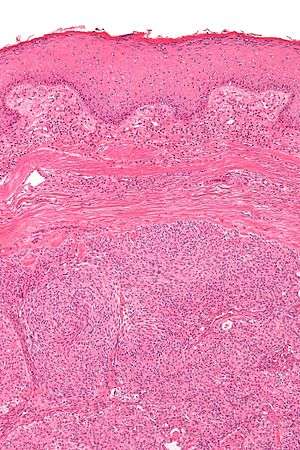

| Micrograph showing an acrospiroma. H&E stain. | |

Hidradenoma(also known as acrospiroma, from akral "peripheral" + spiroma "epithelial tumor of sweat gland") refers to a benign adnexal tumor of the apical sweat gland.[1][2] Another name for Hidradenoma is Cystadenoma and Hydrocystadenomas. These are 1–3 cm translucent blue cystic nodules.It usually presents as a single, small skin-colored lesion, and is considered distinct from the closely related poroma. Hidradenomas are often sub-classified based on subtle histologic differences, for example:

Discussion of sweat gland tumors can be difficult and confusing due to the complex classification and redundant terminology used to describe the same tumors. For example, acrospiroma and hidradenoma are synonymous, and sometimes the term acrospiroma is used to generally describe benign sweat gland tumors. In addition, a single lesion may contain a mixture of cell-types.[2] There has also been a change in understanding about how tumors that were previously believed to strictly derive from specific sweat gland types may, in fact, derive from both eccrine or apocrine glands.[3][4]